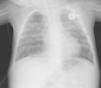

A chest tube was inserted in the left pleura, and by 48h the patient had developed a right pneumothorax requiring placement of another chest tube, with signs of a continuous bilateral air leak. Persistence of the bilateral pneumothorax led to performance of ABPs in the left and right sides on days 40 and 42 of admission, respectively. The air leak ceased immediately in the left hemithorax, and 15min after the procedure in the right hemithorax. The follow-up X-rays showed complete resolution on both sides of the chest (Fig. 2). The patient did not experience pain or other complications from the ABP, and remained asymptomatic at two years’ followup.